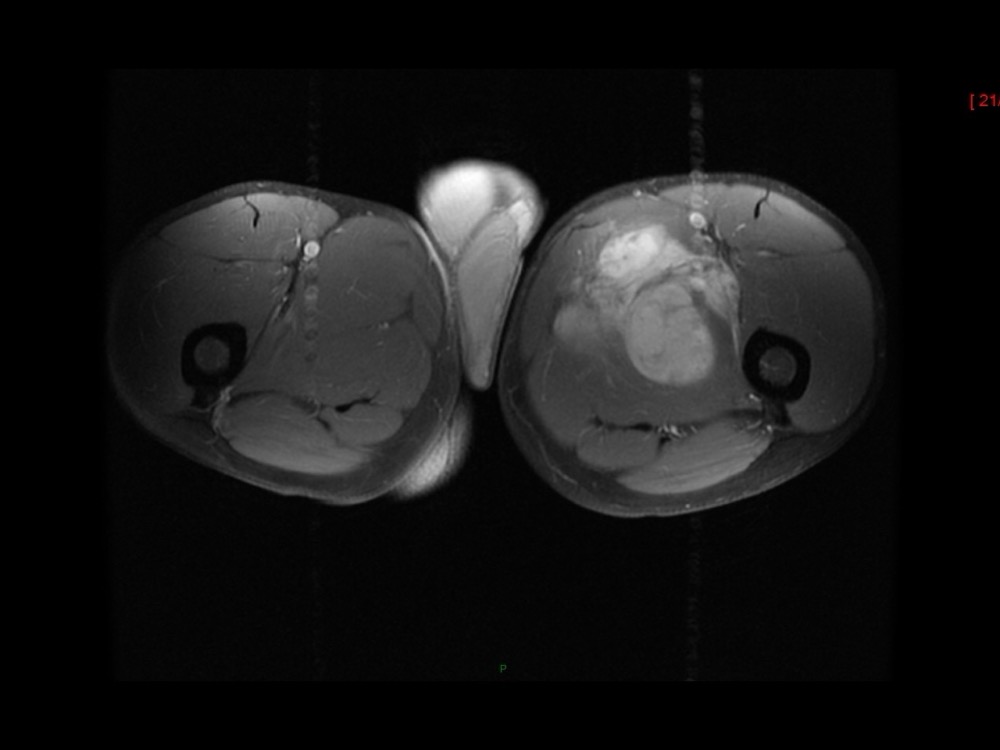

Moalla / Mihoubi-Bouvier / Drapé 18/05/2022